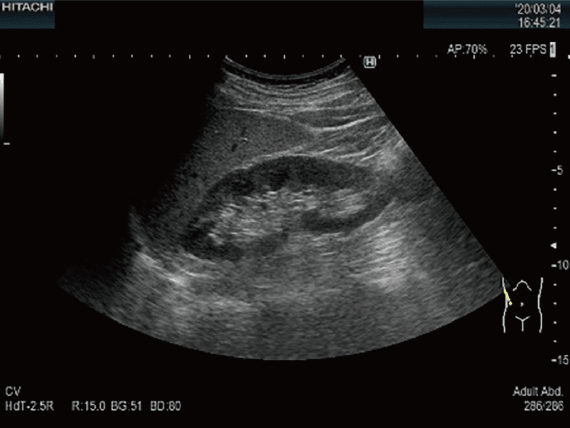

腹部超音波検査

腹部より超音波を照射して,肝臓・胆嚢・膵臓・脾臓・腎臓・大動脈などの腹腔内臓器を観察する検査です。各種臓器の腫瘍をはじめとして,結石,嚢胞,ポリープなどの発見や脂肪肝,肝炎,肝硬変などの各臓器の形態の評価に用いられます。